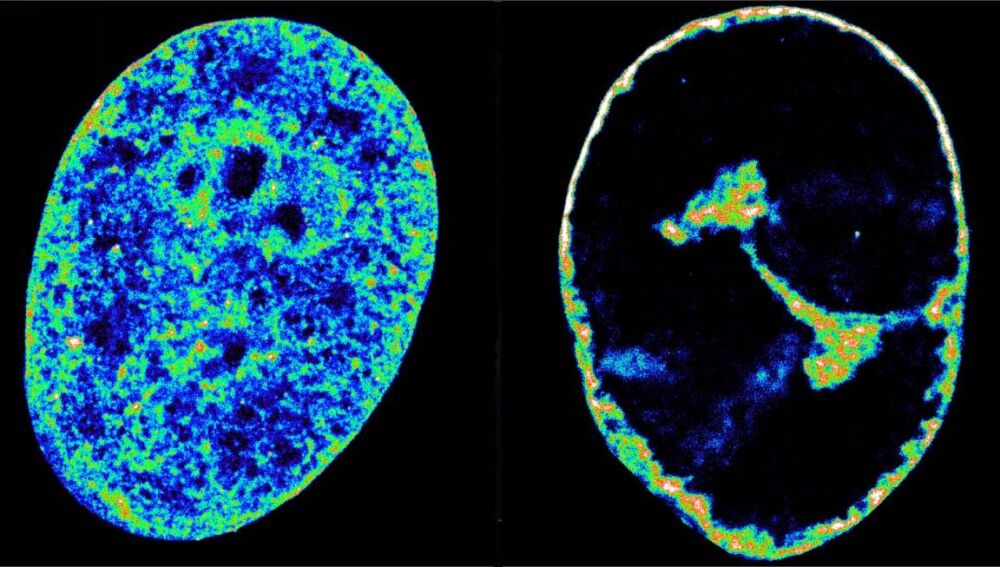

Células humanas antes y después de la infección por el herpes labialSinc

Los hallazgos fueron posibles combinando microscopía de superresolución, una técnica de imagen que puede ver estructuras de 20 nanómetros de ancho (algo aproximadamente 3.500 veces más fino que un cabello), con Hi-C, una técnica que revela qué fragmentos de ADN se están tocando dentro del núcleo. Utilizaron ambas técnicas para entender los mecanismos que usa VHS-1 para secuestrar a las células humanas.

El hurto molecular hace que la transcripción se venga abajo en todo el genoma del huésped, lo que a su vez provoca que la cromatina, el estado natural del genoma humano dentro de las células, se compacte en una cáscara densa de solo el 30% de su volumen original.